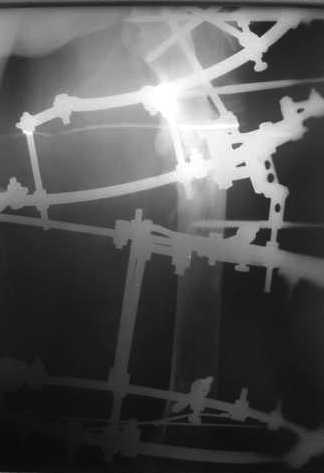

Вчера сделали рентгенограммы бедра нашему пациенту. Угловое смещение нам удалось исправить.

Сейчас проводим дистракцию (2 см).